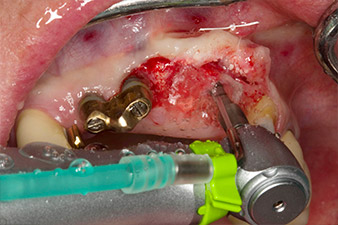

Tapping with the WS-75 L contra-angle handpiece

Fig. 3: Tapping with the WS-75 L contra-angle handpiece at a ratio of 20:1 (programme P4). Implantmed’s high torque, the hexagon chucking system for reliable power transmission and the automatic reversal of the direction of rotation when resistance gets too high prove particularly helpful here.